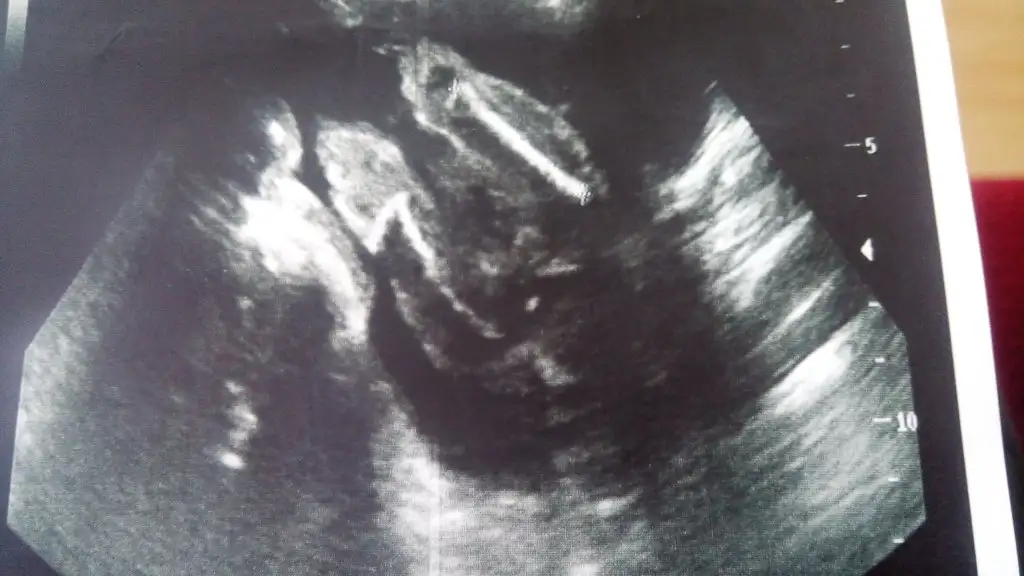

Kızlar bu bebişede bi yorum yaparmısınız arkadaşımın ama doktor büyük ihtimal kız dedi ama bide siz bakın bacak arası resmide var

Eklentiler